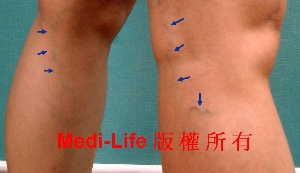

<案例一>

嚴重的靜脈曲張亦是可以輕易解決

嚴重的靜脈曲張亦是可以輕易解決

<案例二>

另一個案例: 手術後三週照片

另一個案例: 手術後三週照片

<案例三>

<案例四>

<案例五>

<案例六>

手術前

手術前 手術後1個半月

手術後1個半月

患者接受極小傷口的 微創 TIPP 靜脈曲張顯微手術, 如箭頭所示, 極為靜脈嚴重鼓張, 甚至小腿因為慢性, 還產生色素沉澱與靜脈潰瘍(venous ulcer). 治療後已改善許多, 曲張扭曲的靜脈消失殆盡, 每個傷口都像抽脂傷口般大小, 約0.2cm!!